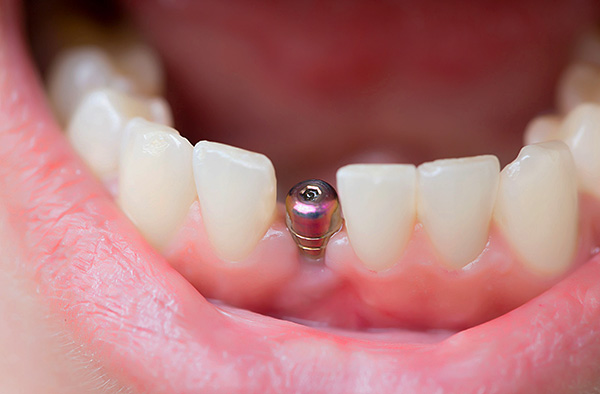

Ecco la protesi sull'impianto: